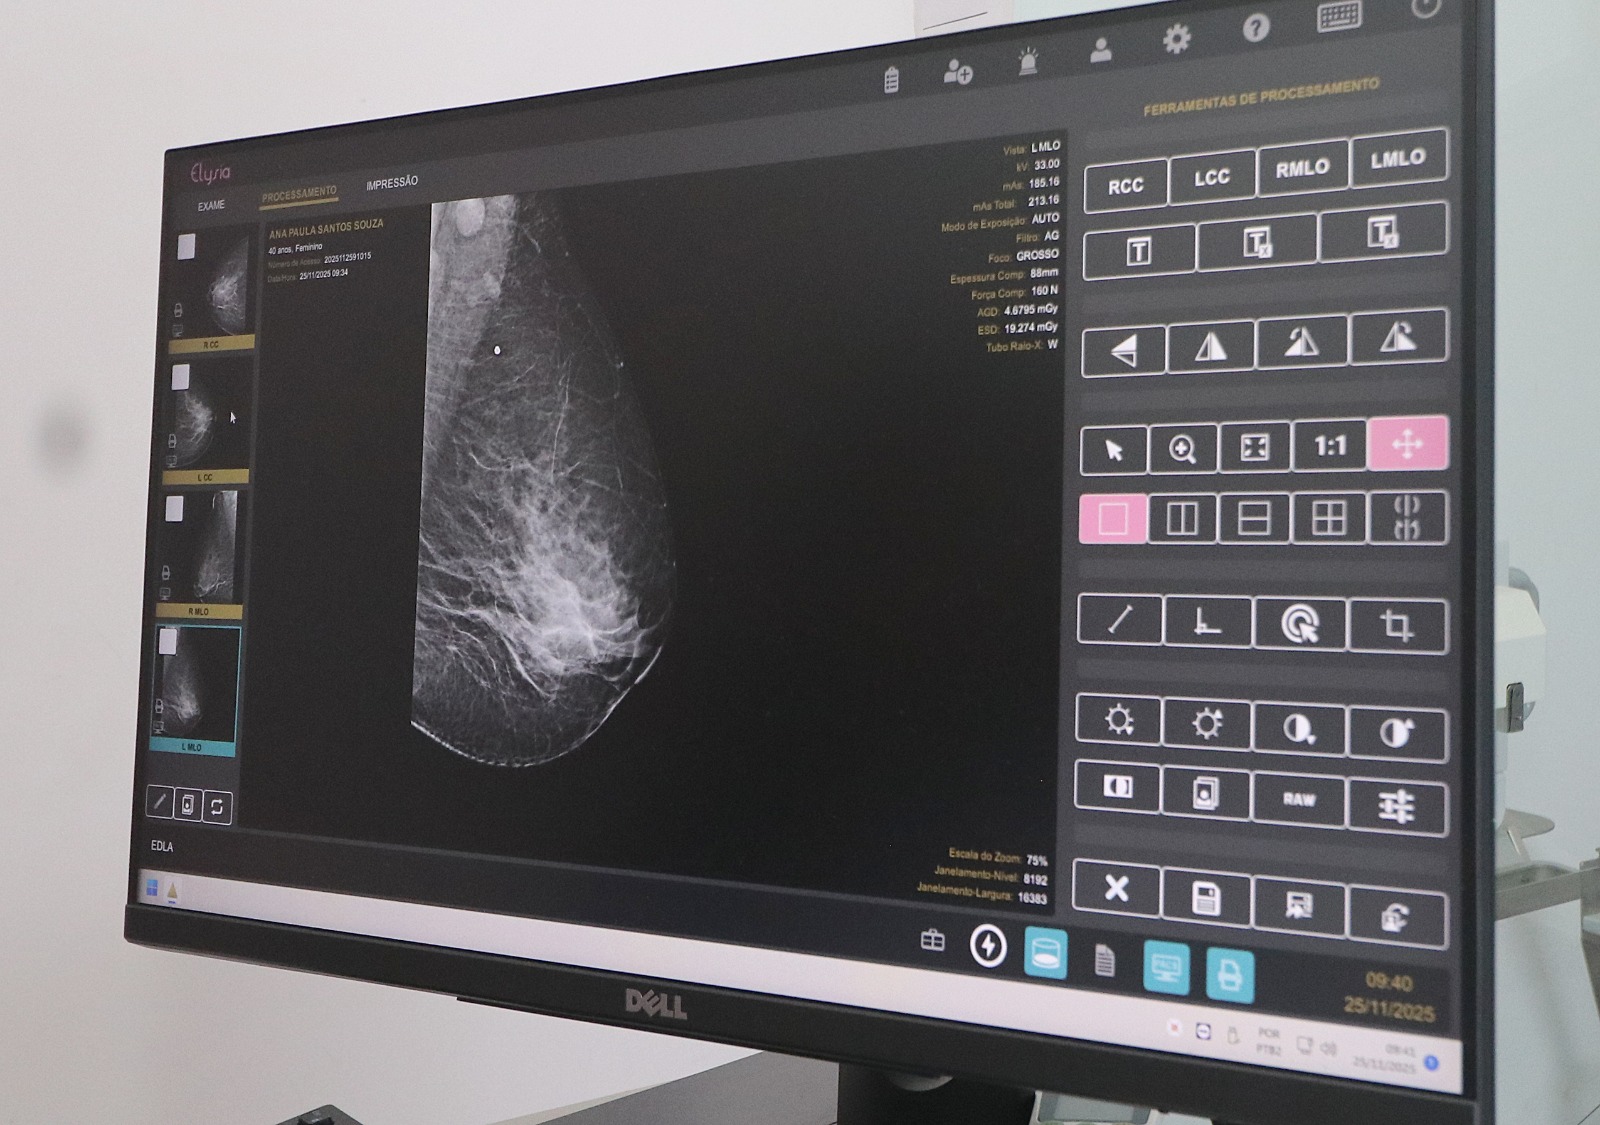

O autocuidado é o primeiro passo para a prevenção. Entre as medidas, está a palpação das mamas uma vez por mês, preferencialmente após o período menstrual, hábito que ajuda a identificar possíveis nódulos, feridas ou retrações na mama. Além disso, o exame de mamografia é considerado o exame de rastreamento mais eficaz para a detecção da doença.

De acordo com a referência técnica médica do Centro de Atenção Integral à Saúde da Mulher (Caism), Myrthis Ribeiro, o exame é simples, rápido, indolor e capaz de identificar alterações que ainda não podem ser percebidas no autoexame. “A recomendação é que mulheres a partir dos 40 anos realizem a mamografia anualmente, ou conforme orientação médica, para aumentar as chances de identificação precoce de nódulos não palpáveis”, destacou.